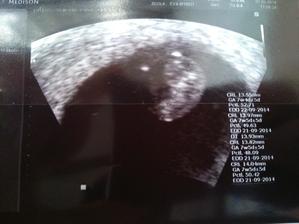

Klokan přiletí ......... v září 🙂

k nám taky 🙂